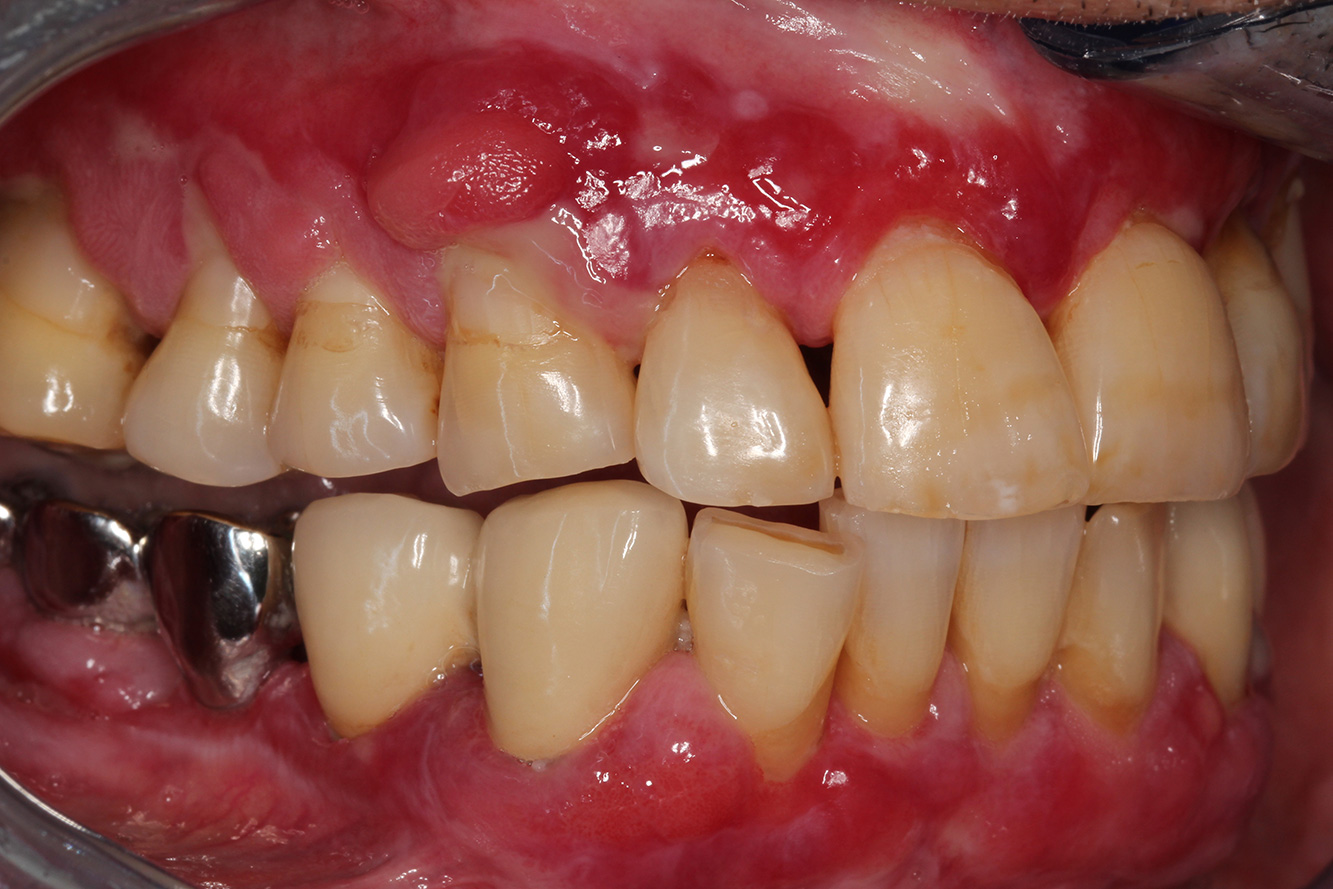

Si presenta un paziente di 71 anni che ha subito un trapianto di reni e con anamnesi di ipertonia (ipertensione). Considerata la sua storia clinica, serve una terapia a lungo termine con ciclosporina che ha un effetto immunosoppressivo e amlodipina che è specifica contro l'ipertensione. Il paziente riporta anche gengive sensibili e sanguinanti. Per quanto riguarda invece lo stato di salute orale, il paziente ha un restauro, presenta un'iperplasia gengivale marcata, una parodontite allo stadio II, grado B con tasche attive e un'iniziale carie radicolare al dente 22 e in più mancano otto denti. Dalla valutazione del rischio di carie si evince un rischio moderato di carie (API 60). Per la seduta di profilassi si possono formulare i seguenti consigli per il trattamento.

Sulla base dell'anamnesi del paziente si può rilevare un rischio particolare di complicazioni. Il paziente è immunodepresso (ciclosporina) in seguito al

trapianto di reni, quindi ha un sistema immunitario debole e necessita di una profilassi contro le infezioni (raccomandazione: 2 g di amoxicillina come antibiotico un'ora prima della seduta). Al tempo stesso, la terapia a lungo termine del paziente si traduce in un rischio aumentato di malattia, perché l'iperplasia gengivale riscontrata è associata proprio a questa terapia (20).

Per questo paziente si consiglia un intervallo di richiamo ravvicinato di tre-quattro mesi. Ciò dipende in larga parte dall'iperplasia gengivale associata alla terapia del paziente, dal fatto che tale iperplasia complica la pratica dell'igiene orale a casa e dal rischio di progressione della parodontite.